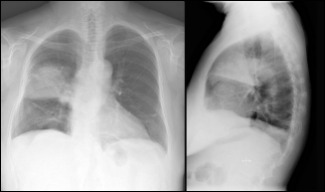

La pneumònia continua essent la primera causa de mort dins de les malalties de causa infecciosa. Per tal d'evitar els tractaments antibiòtics d’ampli espectre, i la conseqüent aparició de resistències, és important diagnosticar-ne el microorganisme responsable. El més...